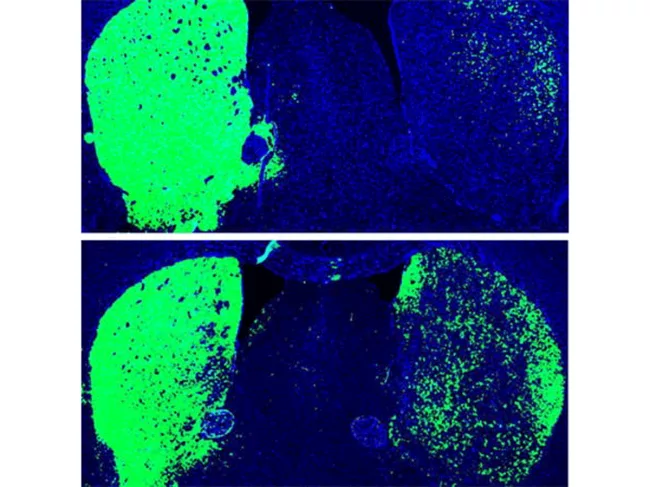

Dopaminergic neurons

ISSCR 2020: In-brain direct reprogramming creates neurons, alleviates Parkinson’s

Two separate groups have recently shown that in mouse models, inactivation of a single gene was enough to directly convert other cell types in the brain into neurons. Read More